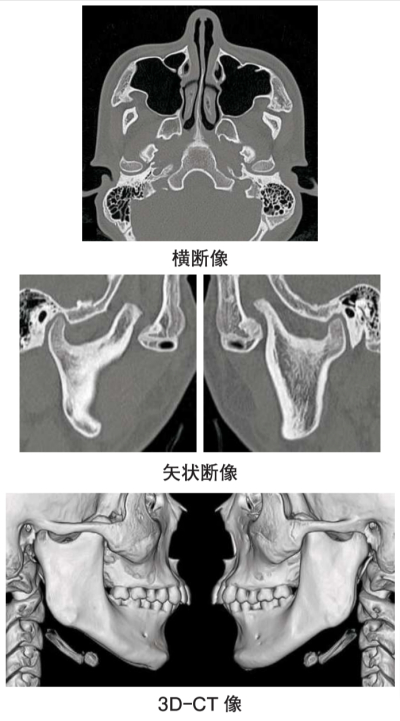

15 歳の男子。口を開けづらいことを主訴として来院した。5年前に気付き、徐々に開きにくくなったという。顎関節部に雑音や痛は認められない。最大開口量は 20 mm であった。初診時のエックス線画像とCT 横断像、矢状断像および 3D-CT 像を別に示す。

診断名はどれか。1つ選べ。

e. 筋突起過長症